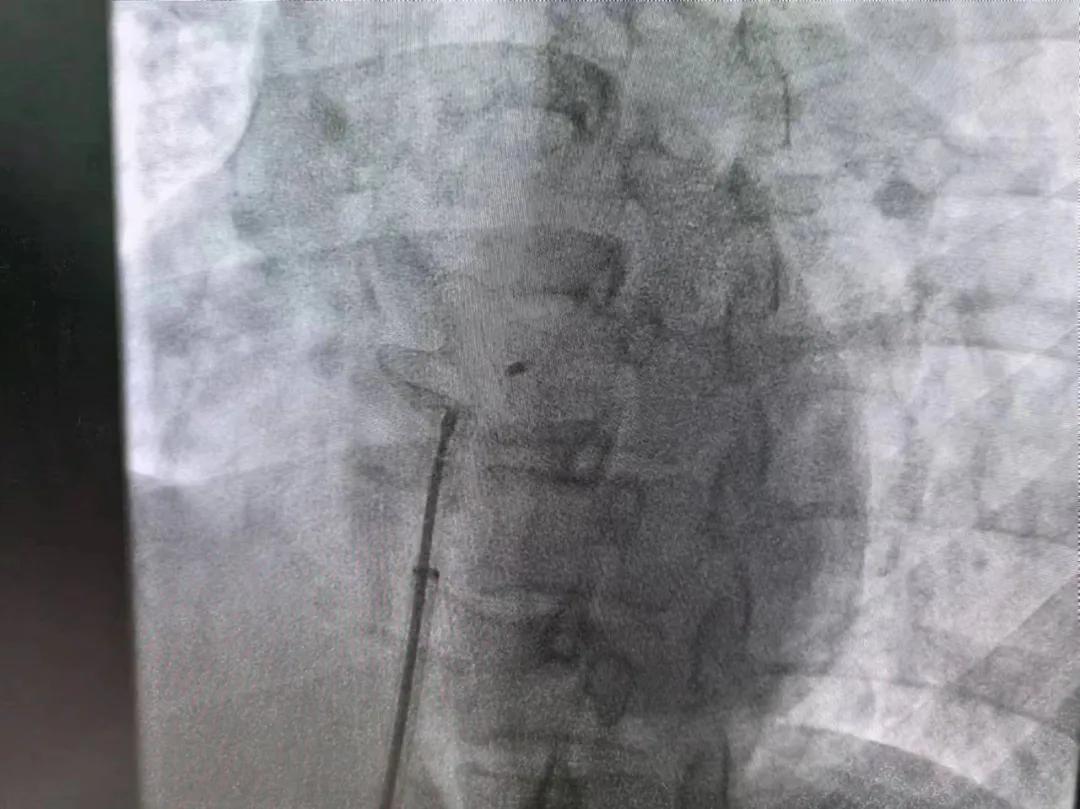

市二院:先天性心臟病介入診療 再創(chuàng)佳績

繼3月14日市二院成功開展首例卵圓孔未閉介入封堵術(shù)之后,3月21日上午,市二院院長王瑾及心血管內(nèi)科主任李慧新帶領(lǐng)心血管內(nèi)科介入團(tuán)隊,再次成功為患者實施“經(jīng)皮房間隔缺損封堵術(shù)”,手術(shù)過程順利。該例病人的成功手術(shù)及康復(fù),標(biāo)志著市二院心血管內(nèi)科在結(jié)構(gòu)性心臟病介入診療中再次達(dá)到了新高度。

患者為中年女性,41歲,近2年一直反復(fù)出現(xiàn)頭暈、頭痛,曾先后在多家醫(yī)院就診。近期患者癥狀加重,出現(xiàn)活動后氣喘合并胸悶癥狀,來到心血管內(nèi)科就診。經(jīng)心臟彩超檢查顯示:患者房間隔下段連續(xù)性中斷,缺損直徑達(dá)到了13mm,肺動脈壓已經(jīng)輕度增高,確診為房間隔缺損。

對于房間隔缺損面積較大的患者,如果長時間不注意,不及時介入封堵治療,心功能可能會出現(xiàn)嚴(yán)重問題,一旦出現(xiàn)嚴(yán)重肺動脈壓高壓及心力衰竭,將喪失診療機(jī)會,會嚴(yán)重降低患者生活質(zhì)量,且極大縮短患者壽命。

于是,院長王瑾會診后,詳細(xì)詢問患者病史,認(rèn)真分析臨床癥候群并準(zhǔn)確診斷,耐心做好患者及家屬病情告知和充分溝通。經(jīng)過完善的術(shù)前評估及準(zhǔn)備,心血管內(nèi)科介入團(tuán)隊成功為患者實施“經(jīng)皮房間隔缺損封堵術(shù)”,手術(shù)過程順利。近日,患者已順利康復(fù)出院。 (尹紅婭 潘長林)